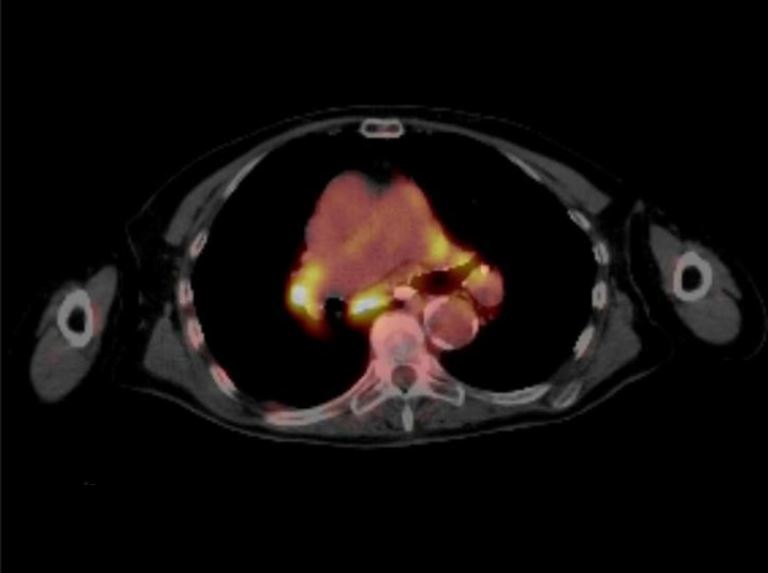

CT and PET scans both have false positives and negatives, he said. So if physicians rely on imaging alone, the cancer's stage, or determination of whether the disease has spread, might be classified incorrectly. That misclassification can inadvertently result int providing patients with either the wrong or less-than-optimal treatments, he said.